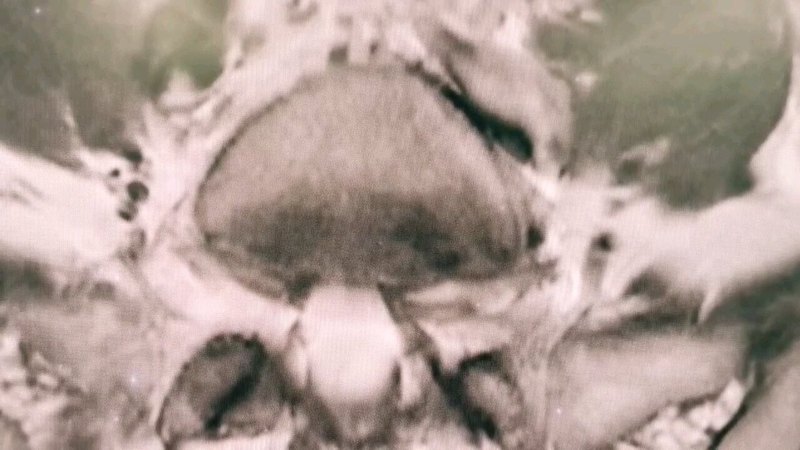

治療前病人是一位64歲的阿姨,在當(dāng)?shù)蒯t(yī)院檢查發(fā)現(xiàn)胸9水平脊髓腫瘤,根據(jù)影像學(xué)特征,考慮脊膜瘤可能性很大治療中仔細(xì)分析影像學(xué)資料,可以發(fā)現(xiàn)腫瘤占據(jù)了胸9水平椎管內(nèi)空間的90%以上,正常脊髓受壓非常嚴(yán)重,被腫瘤推擠到右側(cè)不到10%的空間。腫瘤的基底在左側(cè)硬脊膜,術(shù)中先電凝切斷腫瘤基底部的血供。從技術(shù)上來(lái)說(shuō),切除腫瘤不困難,手術(shù)的難點(diǎn)和關(guān)鍵在于切除腫瘤的同時(shí),必須要保護(hù)好第九胸椎水平菲薄的正常脊髓組織。我們?cè)陲@微鏡下先充分銳性分離腫瘤周?chē)闹刖W(wǎng)膜,然后在正常脊髓無(wú)張力的情況下分塊切除腫瘤,腫瘤全部切除。腫瘤與正常脊髓之間的膜性結(jié)構(gòu)完整保留。治療后治療后即刻切除腫瘤后,正常脊髓組織、神經(jīng)根以及被腫瘤推擠移位的脊髓血管完好保留。術(shù)后麻醉蘇醒,病人四肢肌力5級(jí),無(wú)任何神經(jīng)功能障礙。